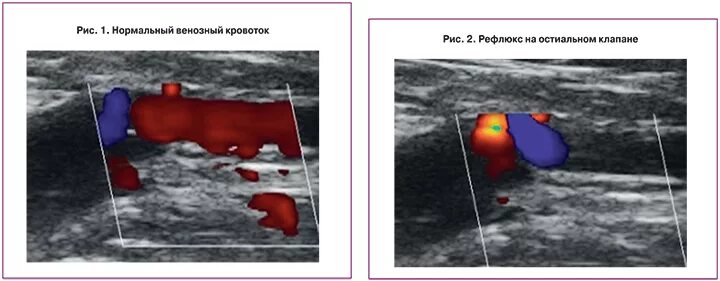

Венозна протока